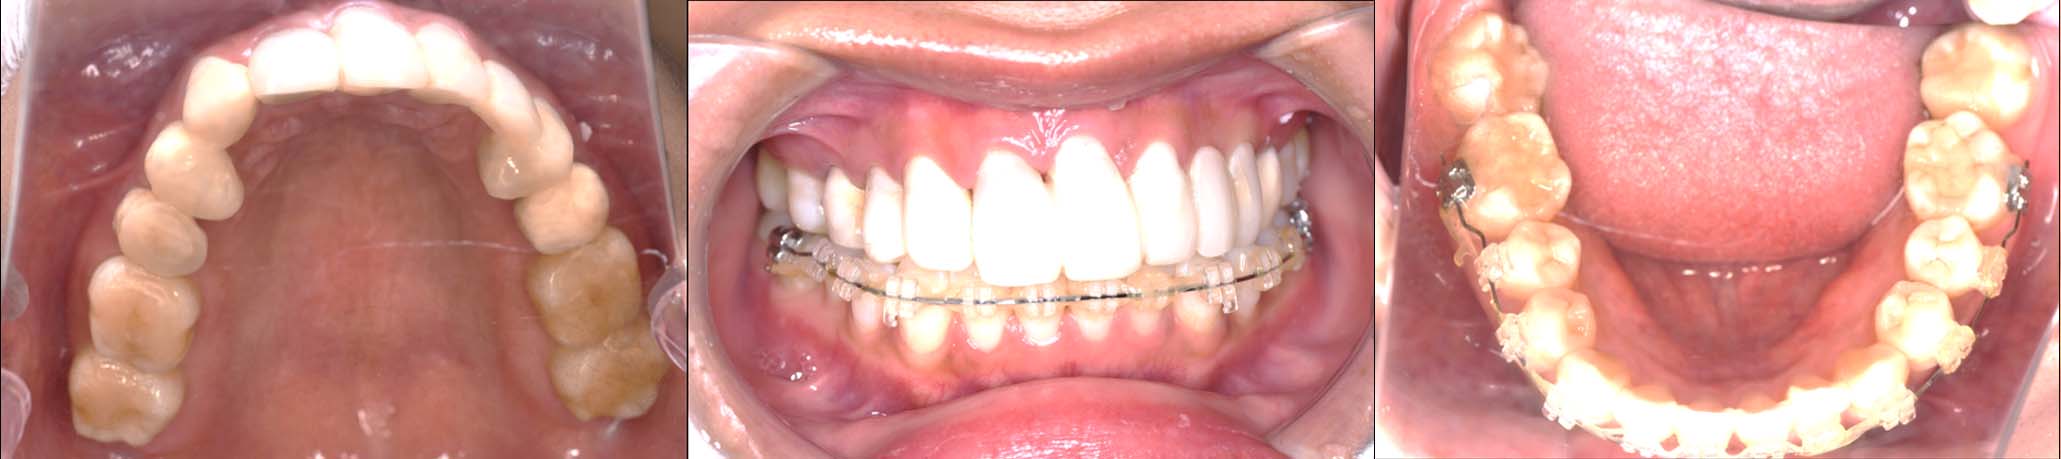

2024年 10月 下顎MTM開始

2024年 10月10日

10月21日

11月7日

11月28日

12月16日

12月23日

1月9日

1月30日

2月20日

3月13日

4月24日

9月25日